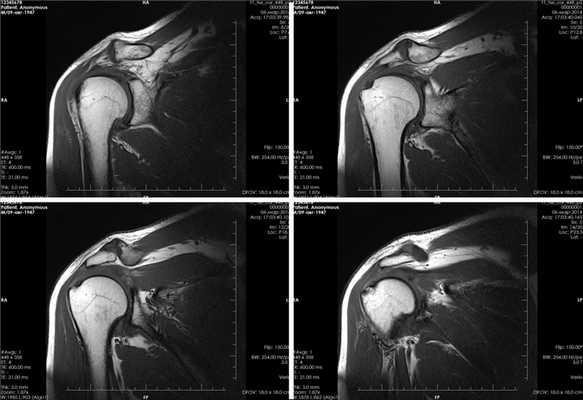

Вывих плеча на МРТ

Вывих плеча - одна из самых часто случающихся травм верхних конечностей. Он может быть первичным (свежим) и привычным. Магнитно-резонансная томография позволяет выявить повреждения в суставе и его связочном аппарате при обоих видах вывиха.

Первичный вывих плеча на МРТ

Первичный вывих плеча - это травма, возникшая, как правило, при механическом воздействии на сустав, в том числе, полученная в результате интенсивных физических нагрузок. Первичный вывих часто называют свежим. МРТ плечевого сустава визуализирует структуру сустава, соединяющего плечевую кость с костями, образующими пояс верхней конечности (ключица, лопатка), а также окружающих его тканей. На снимках, полученных в ходе МРТ, видны связки, мышцы, сухожилия, сосуды и нервы.

Привычный вывих плеча на МРТ

Привычный вывих плеча - одно из проявлений патологических процессов, происходящих в связочном аппарате сустава. Привычный вывих способна вызвать даже минимальная травма или повседневные действия. В таком случае обследование может быть проведено для определения степени разрыва капсулы сустава, связок и мышц или уточнения результатов рентгенографии и КТ, которые диагностируют повреждения костей наряду с МРТ. Признаками привычного вывиха плеча являются: травма сухожилий и подлопаточной мышцы, разрыв сегмента суставной губы и синовит. При вывихе МРТ необходима также для диагностики сдавливания сосудов и нервов плеча.